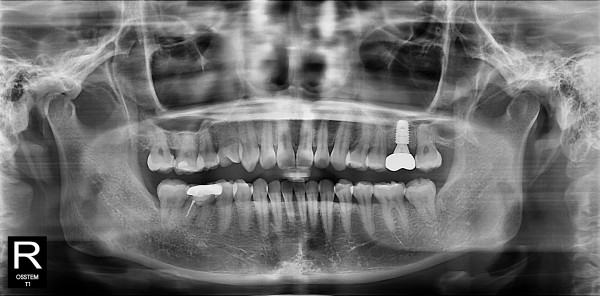

사랑니발치 20대/여성

5e20e086184bc11a2d853605b7813944_1764319752_9378.jpg